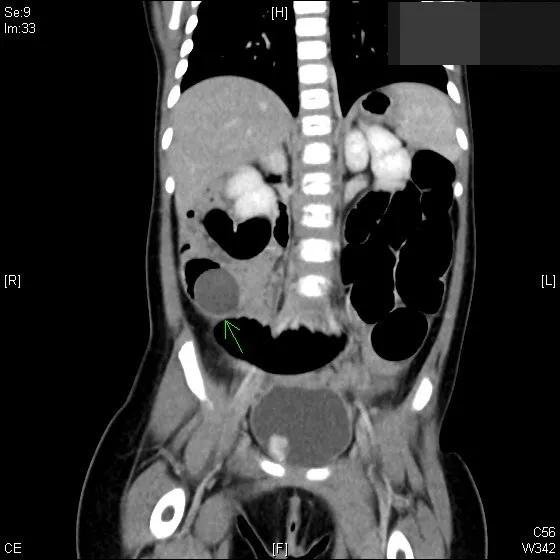

經安排X光、電腦斷層等檢查,賴宛孜發現男童小腸有多段腫脹現象,會小兒外科醫師蔡逸文為男童開刀。蔡逸文指,經剖開男童小腸段,發現裡面有多顆脹大的水晶寶寶,已將小腸阻塞,其中最大一顆橢圓形水晶寶寶,竟然有2乘以3公分大,這是男童為何會嘔吐、吃不下原因,取出腸內異物後,留男童住院觀察。

男童術後一度可進食,但2、3天後,又開始嘔吐、吃不下,賴宛孜再為男童檢查,發現還有水晶寶寶阻塞住腸道,因此在術後第5天,由蔡逸文再為男童開第2次刀。

蔡逸文說,第2次手術時,他發現男童的小腸又出現新的阻塞段,「腸子鼓地大大的」,一樣剖開後看到多顆已膨脹的水晶寶寶。